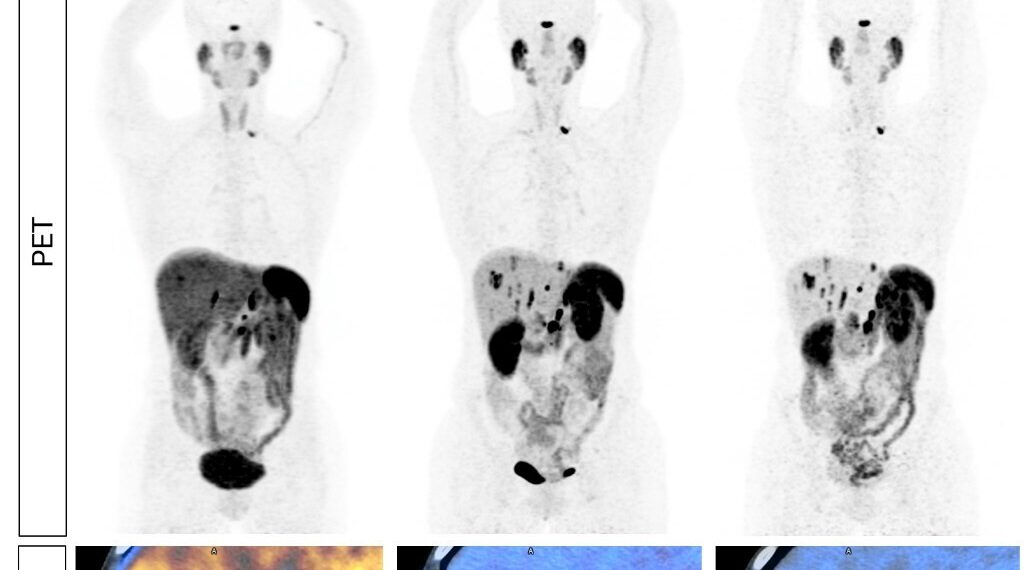

Figure 1: 59-year-old participant with functional NETs. 68Ga-DOTATATE PET/CT was performed 26 days prior to the 64Cu-SARTATE PET/CT (same-day imaging). PET (top images): top left image shows higher background on the 68Ga-DOTATATE PET. Top centre and right PET images show multiple lesions detected by 64Cu-SARTATE against a low background. Images are shown as maximum intensity projections. PET/CT fusion (bottom images): axial sections show intense liver uptake on the 68Ga-DOTATATE PET/CT (bottom left), which limits the ability to distinguish lesions from the background, and 3 clearly defined lesions are visible on the 64Cu-SARTATE PET/CT (arrows; bottom centre and right images, same-day and next-day imaging, respectively). Mean maximum standardised uptake value (SUVmax) of lesions shown in the 64Cu-SARTATE PET/CT images: 16.1 and 16.5 on same-day and next-day imaging, respectively. Lesions in the liver have been verified as true-positive based on other scans, including diagnostic CT and magnetic resonance imaging (MRI). Fused images are shown with consistent scaling for visual comparison.

Out of all lesions identified by the readers, 230-251 were deemed to be discordant between 64Cu-SARTATE and 68Ga-DOTATATE PET/CT, with 93.5% (average across readers and imaging days) of these discordant lesions detected on the 64Cu-SARTATE scans only. A previously completed Phase I study demonstrated a 1.7 fold increase (median of 6.70 vs. 3.92, p=0.002) in contrast (i.e. lesion-to-background ratio) for 64Cu-SARTATE PET/CT performed at 4 hours post-administration compared to 68Ga-DOTATATE PET/CT2. This improvement in contrast may explain the detection of additional lesions observed in the DISCO trial. The average SUVmax, representing the highest concentration of 64Cu-SARTATE uptake in lesions, was notably high, ranging from 37.42 to 43.90 across both imaging days in the DISCO trial.

Clarity’s Executive Chairperson, Dr Alan Taylor, commented, “We are very excited about the initial topline data from the DISCO trial as 64Cu-SARTATE was confirmed to be safe and very effective in detecting NET lesions in patients with known or suspected disease. The DISCO trial demonstrates a significant advantage of our diagnostic over 68Ga-DOTATATE. 64Cu-SARTATE detected almost double the number of lesions compared to the SOC, and, where SOT was available, a very high lesion-level sensitivity of 93.4% – 95.6% in comparison to just 4.4% – 6.6% for 68Ga-DOTATATE for these discordant findings. In addition to identifying more lesions with our product, lesions detected by 64Cu-SARTATE also exhibited high uptake with low background on the PET scans, making it easier to identify those lesions by readers. Excellent lesion visualisation was also supported by substantial clearance from the liver. The favourable biodistribution of 64Cu-SARTATE PET enabled high-contrast diagnostic imaging for up to approximately 24 hours post-injection (Figure 1), offering greater flexibility in the scheduling of PET/CT scans.